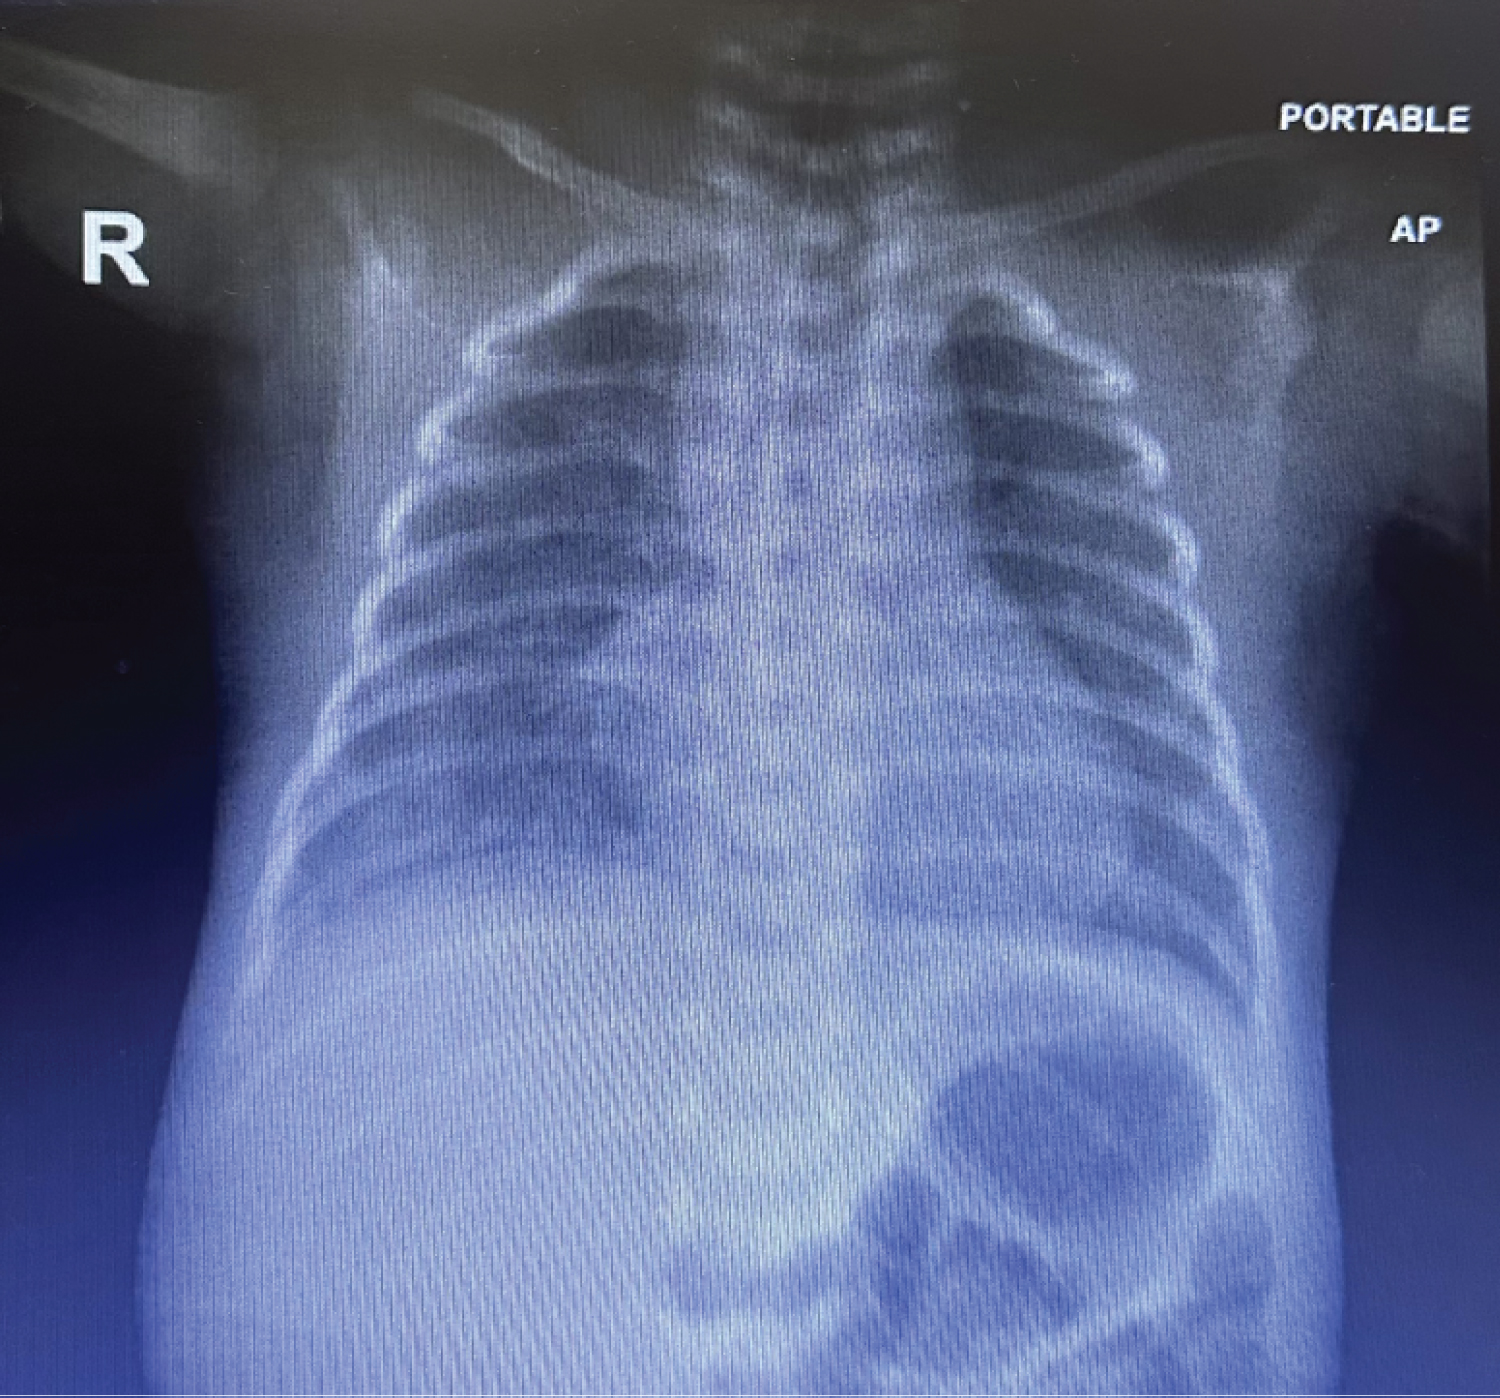

Figure 1: CXR: Increased lung markings in both lungs with mild haziness in both lower zones, more in right side. View Figure 1

Chest Radiography showed: Increased lung markings in both lungs with mild haziness in both lower zones, more in right side. Blood pressure was within normal limits. In whole blood count analysis hemoglobin, leukocyte and platelet counts were 11.5 g/dl, 8834/mm 3 and 176000/mm, respectively. C-reactive protein was 24 mg/L. Then increased over 18 hrs to 42 mg/L.